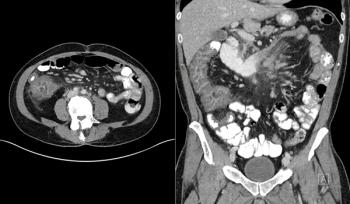

A 56-year-old woman presents with abdominal fullness and virilization. Axial and coronal images from a CT scan of her abdomen are shown below. What is your diagnosis?